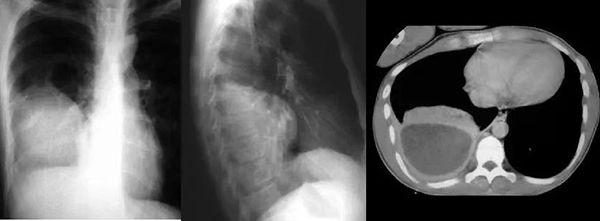

近日,一位70岁男性患者,因“反复咳喘3余年,加重1周”住院治疗。患者入院后行胸部CT提示右侧大量胸腔积液,进一步完善胸腔彩超提示:右侧包裹性胸腔积液。患者胸闷、气短症状明显,偶有痰中带血情况。抗感染治疗效果不佳。

为进一步明确诊断、改善患者症状,拟行包裹性积液胸腔穿刺置管引流术。但常规胸腔穿刺引流极易造成穿刺损伤及穿刺失败风险,较以往相比因技术难度和风险高。史淑利医生与青南支医专家范得艳医生综合分析患者病情后,决定联合超声科为患者行床旁超声引导下包裹性胸腔积液穿刺置管引流术。在手术过程中,由超声科医生首先对包裹性积液进行定位,由史淑利医生亲自为患者进行胸腔积液穿刺置管术,手术顺利完成。整个过程如同一场精细的外科手术,每一个步骤都严谨而准确。术后史淑利医生向年轻医生进行了胸腔穿刺术和胸腔积液的教学查房,向她们讲解胸腔穿刺的适应症、禁忌症、注意事项、可能出现的不良反应及处置方案,胸腔积液鉴别诊断。通过胸水结果分析,患者明确诊断“肺结核;结核性胸膜炎”,为患者制定了正规的抗结核治疗及随访方案。患者胸闷、气短症状得以缓解,患者及家属对治疗效果非常满意,对我院医护人员的专业技术和精心护理给予了高度赞扬。